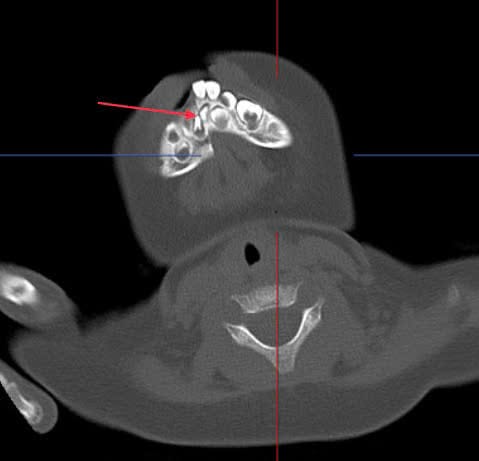

Bệnh nhi tên là T.P.C (13 tháng tuổi, Hoàng Mai, Hà Nội) nhập viện trong tình trạng chảy nhiều máu vùng miệng do ngã úp mặt từ xe đẩy xuống đất. Ngay sau khi tiếp nhận, các bác sĩ tiến hành giảm đau, chỉ định chụp cắt lớp vùng hàm mặt. Kết quả cho thấy cháu bị gãy rời di lệch thân xương hàm dưới kèm sưng nề - tụ khí phần mềm xung quanh. Bệnh nhi bị gãy lồi cầu bên trái xương hàm dưới, đường gãy đi vào diện khớp.

Bệnh nhi C. được chuyển ngay sang điều trị tại Khoa Răng Hàm Mặt, Bệnh viện Đại học Y Hà Nội. Sau quá trình thăm khám và hội chẩn toàn khoa, Lãnh đạo khoa Răng Hàm Mặt đã quyết định tiến hành phẫu thuật sớm nhất có thể để khắc phục tình trạng của bệnh nhi.

Do tính chất đặc biệt của trường hợp, các bác sĩ đã tiến hành bàn bạc kỹ lưỡng để đưa ra phương án phẫu thuật tối ưu nhất cho bệnh nhi. Để tiết kiệm thời gian và giảm thiểu các thủ tục phức tạp, thay vì chuyển máng phẫu thuật về xưởng phục hình răng, các bác sĩ và kỹ thuật viên đã phối hợp thực hiện ngay công đoạn chế tác máng phẫu thuật tại khoa.

Theo ThS.BSNT Dương Chí Hiếu – Khoa Răng Hàm Mặt, Bệnh viện Đại học Y Hà Nội, người đã trực tiếp tiến hành phẫu thuật nắn chỉnh, cố định xương hàm cho biết; do bệnh nhi chỉ mới 13 tháng tuổi nên việc thực hiện phẫu thuật đòi hỏi kỹ thuật chuyên sâu và sự cẩn trọng đặc biệt. Các thao tác được thực hiện nhẹ nhàng, tỉ mỉ để đảm bảo an toàn cho bệnh nhi, đồng thời giảm thiểu tối đa sự xâm lấn và tổn thương. "Việc lựa chọn phương pháp gây mê phù hợp và thời gian thực hiện phẫu thuật ngắn cũng là yếu tố quan trọng giúp bảo vệ sức khỏe và tạo điều kiện cho quá trình hồi phục nhanh chóng" BS Hiếu cho hay.